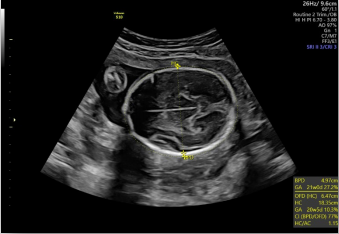

生長指標半自動測量

在合適切面下,可自動識別測量臨床所需的胎兒雙頂徑,頭圍,腹圍,股骨長和肱骨長度等多個參數(shù)。